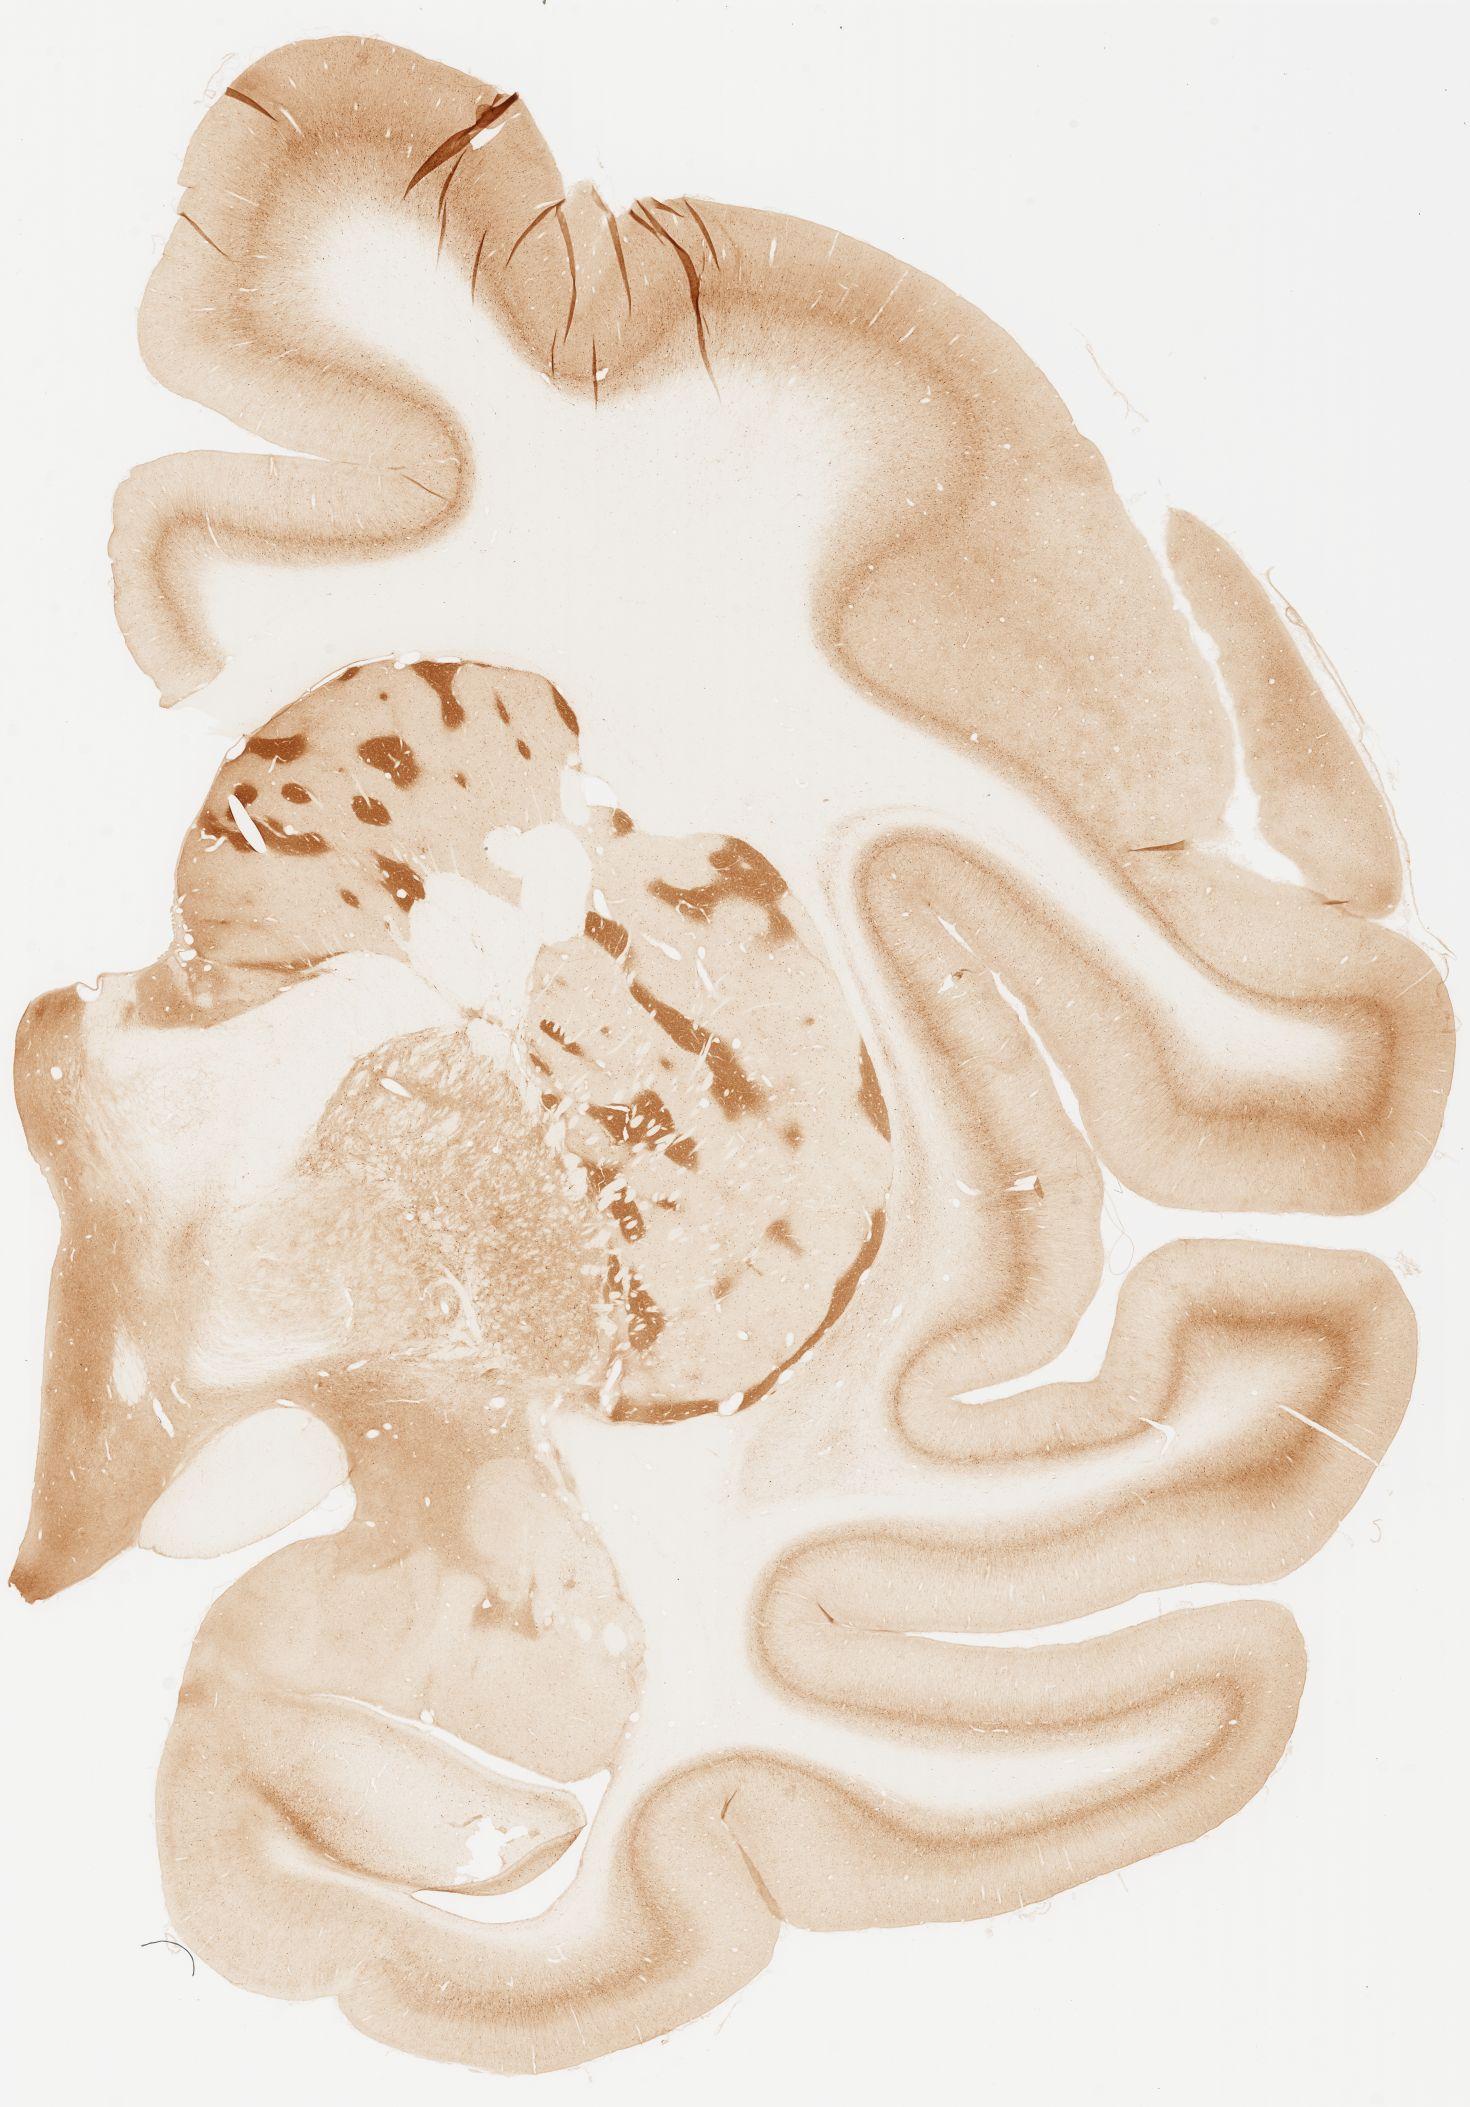

Datasets -> Macaca Fascicularis -> KChIP1, (Potassium Voltage-Gated Channel-Interacting Protein 1), coronal, immuno, Whole-Brain, adult

[ Metadata ]   ·   Source: Edward G. Jones